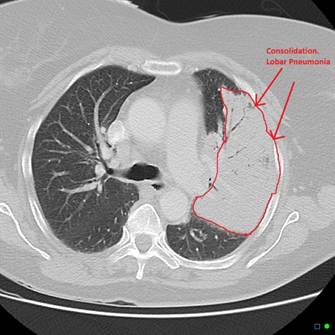

Viêm phổi: phế nang bị lấp đầy bởi dịch viêm, vi khuẩn và tế bào miễn dịch. Hình ảnh thường thấy là đông đặc phổi. Lâm sàng biểu hiện sốt, ho, khạc đàm, đau ngực kiểu màng phổi và khó thở [1]. Mức độ ảnh hưởng phụ thuộc vào diện tích phổi bị tổn thương.